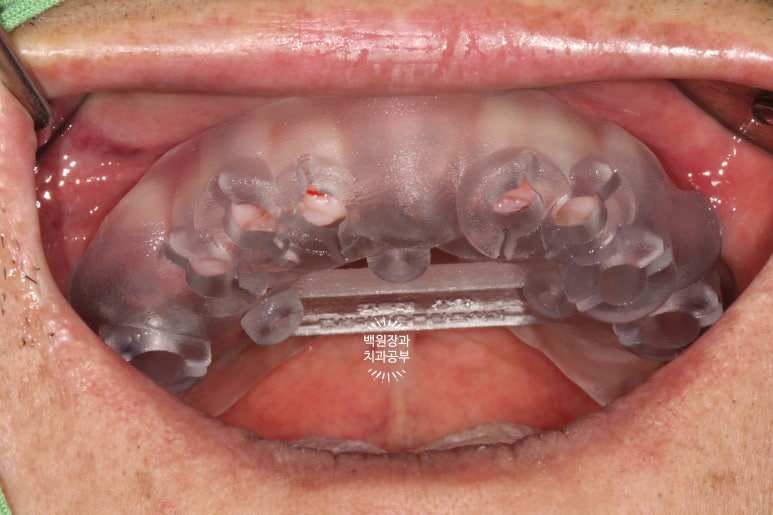

임플란트 2차수술을 하면 이렇게 임플란트 위치를 확인하실 수 있게 됩니다.

그리고 잘 유지된 각화치은의 양을 확인하실 수 있죠.

처음 내원하셨을 때 임플란트 주위염이 심했던 1개의 임플란트를 제외하고 3개의 임플란트는 이제 치아 머리를 얹어 새로운 쓰임을 기다리고 있는 중입니다.

임플란트를 몇 개 심고나니 뭔가 위치가 더 조화로워 보이지 않나요?

씹는면에서 본 임시치아입니다.